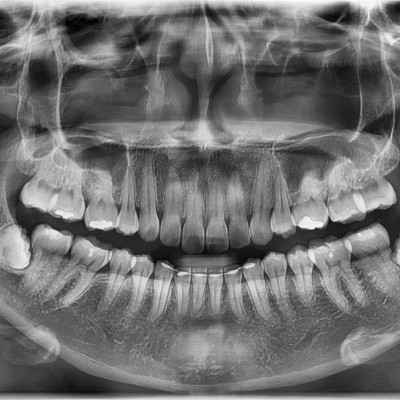

#18,28,38,48 사랑니 발치 #18,28,38,48 사랑니 발치 구강 외과 전문의가 당일 발치했습니다. ------------------..

작성자 이턱이 작성일 01-29 조회 5